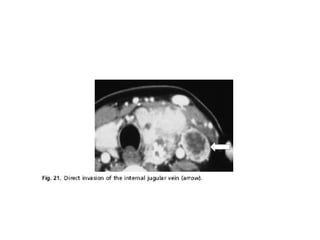

 Invasión vascular

 Es rara la invasión de los vasos del cuello y mediastino

en una lesión que pudiera ser resecable.

 La excepción es la afección de la vena yugular interna, la

cual puede ser resecada sin consecuencias importantes.

 El escenario clínico más frecuente en el que se ve

afectada la vena yugular interna es en la que es invadida

por extensión directa de una ganglio con metástasis.

 También se ha descrito infiltración intraluminal vía

diseminación del drenaje venoso.

• 45.

 Invasión vascular Es rara la invasión de los vasos del cuello y mediastino en una lesión que pudiera ser resecable.  La excepción es la afección de la vena yugular interna, la cual puede ser resecada sin consecuencias importantes.  El escenario clínico más frecuente en el que se ve afectada la vena yugular interna es en la que es invadida por extensión directa de una ganglio con metástasis.  También se ha descrito infiltración intraluminal vía diseminación del drenaje venoso.